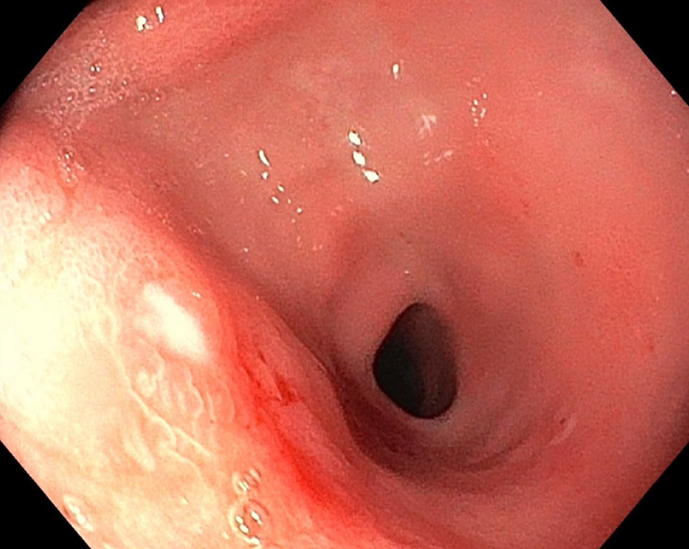

Figure 3 A 34-month-old girl who underwent a liver transplant 6 months ago presented with pale, hypoalbuminemia, and mucous diarrhea.

Esophagogastroduodenoscopy and colonoscopy revealed generalized mucosal swelling with multiple shallow ulcers in the stomach and duodenum. Histopathological examination revealed an atypical lymphoproliferative lesion extending from the stomach to the rectum.